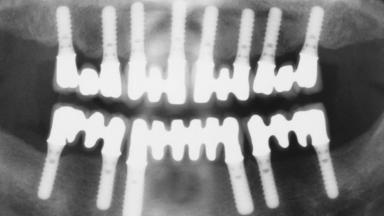

Immediate Loading of Eight Implants in the Maxilla and Six Implants in the Mandible and Final Restoration with Three-Unit and Four-Unit FDPs

# of Implants 14

Type of Implants One-Piece

Defining Characteristics Fully edentulous upper jaw to be rehabilitated with four or more implants

Modality 6+ implants with immediate loading

Bone Volume Horizontally and vertically sufficient